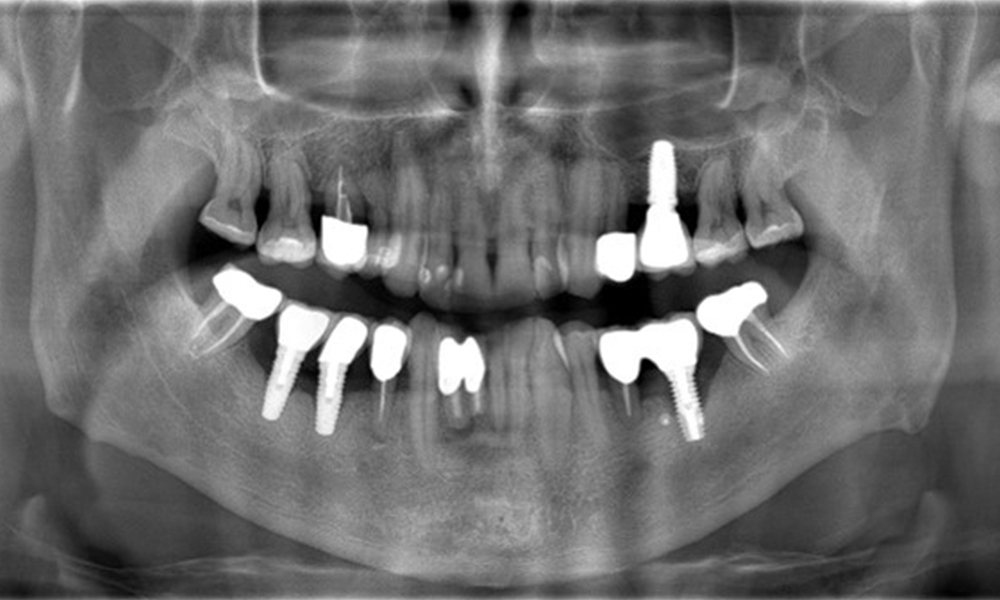

52-годишен пациент се явява на профилактичен преглед. Пациентът няма хронични заболявания и не приема никакви лекарства. Претърпял е различни дентални лечения и също така има две активни кариозни лезии. Освен това има четири импланта (2-ри, 3-ти и 4-ти квадрант). Установява се, че има ранно пародонтално заболяване (стадий IV, степен В). Състоянието на пародонта е стабилно, като дълбочина на сондиране (ST) от 5 mm се проявява само при импланта в област 36. Установен е и гингивит.

Рентгеновите снимки показват прогресията на костната загуба. ОПГ от 29.06.2020 г. (вляво) и ОПГ от 26.02.2024 г. (вдясно).

ОПГ: 26/02/2024 Дентална рентгенова снимка: 18/01/2024

Рентгеновите снимки показват прогресията на костната загуба.